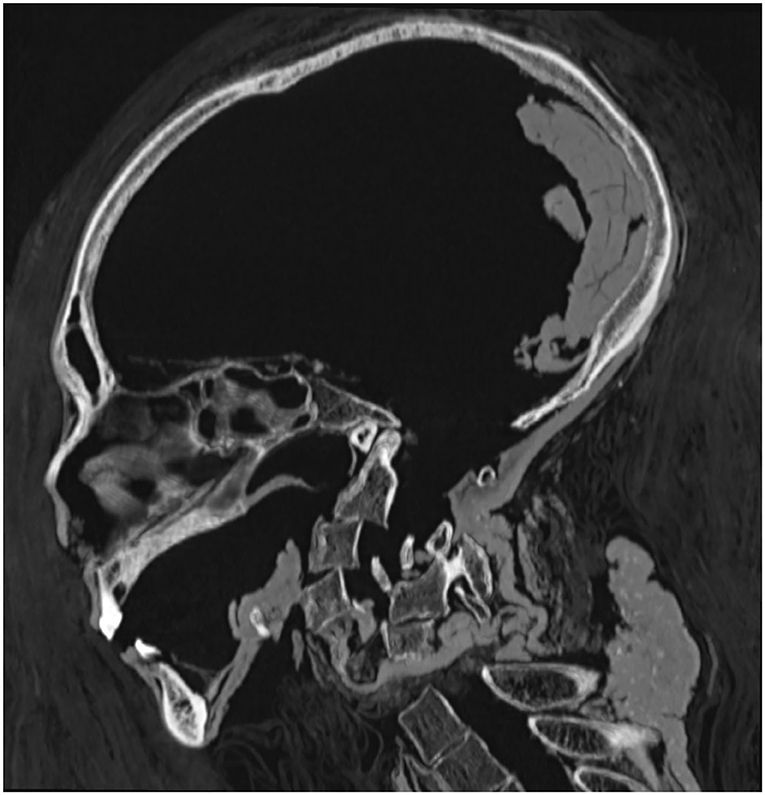

Debajo de las sábanas de lino envueltas transversalmente que bajaban en espiral por el cuerpo de la cabeza a los pies, se hizo evidente el trabajo de los embalsamadores. Una incisión vertical de nueve centímetros realizada en el costado inferior izquierdo de Amenhotep I indicó evisceración (extirpación de órganos); la cavidad abdominal inferior se rellenó con lino tratado con resina. Sin embargo, no se extrajo el corazón ni el cerebro, que se descubrió intacto, descansando en la parte posterior del cráneo.

La momia de Amenhotep I fue descrita con una cara ovalada con ojos hundidos y mejillas colapsadas. Su nariz es pequeña, estrecha y aplanada, mientras que sus dientes sobresalen levemente. Sus orejas son pequeñas con un pequeño piercing en el lóbulo izquierdo. En particular, se ven algunos mechones de cabello enrollados en la parte posterior y los lados de la cabeza.